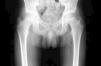

El caso que exponemos, tiene la presentación típica del arrancamiento de la espina iliaca antero-inferior (EIA-I), pero la lesión no fue evidente en la proyección antero-posterior de la cadera. Se trata de un joven de 13 años, sin antecedentes patológicos de interés, que se presenta a la consulta de pediatría con cojera de 2h de evolución. Refiere un dolor a nivel de la región inguinal derecha de aparición súbita, justo cuando fue a golpear un balón de futbol durante el recreo escolar; el dolor no se irradia, es de intensidad leve y está bien localizado. El estado general del paciente es bueno, no tiene fiebre ni padeció enfermedades infecciosas en días previos. La cadera derecha no presenta actitud en flexión ni rotación externa. Los movimientos activos están limitados por dolor, pero la flexión y rotación pasiva no tenían limitación del arco del movimiento. No se palpaba ninguna masa ni era evidente ningún hematoma superficial a nivel de la región inguinal derecha. El resto de la exploración física era normal. Se le solicitó una radiografía de cadera antero-posterior (fig. 1) en la cual no se observó ninguna lesión, y una axial derecha (fig. 2) que permitió llegar al diagnóstico de una fractura por avulsión de la EIA-I. Notar que la lesión en esa proyección fue evidente porque la técnica fue más oblicua que axial, tal como lo demuestra la asimetría de los agujeros obturadores. Se realizó una interconsulta a traumatología infantil, indicando reposo relativo, uso de muletas durante los primeros 15 días para reducir la carga del peso durante la deambulación, analgésicos, y reincorporación a la actividad física controlada a partir del primer mes de evolución. Expresamente se le indicó que evite la práctica de futbol durante al menos 3 meses. Se le realizó el primer control clínico a las 2 semanas del traumatismo, y el paciente ya conseguía caminar y subir escaleras sin presentar molestias.